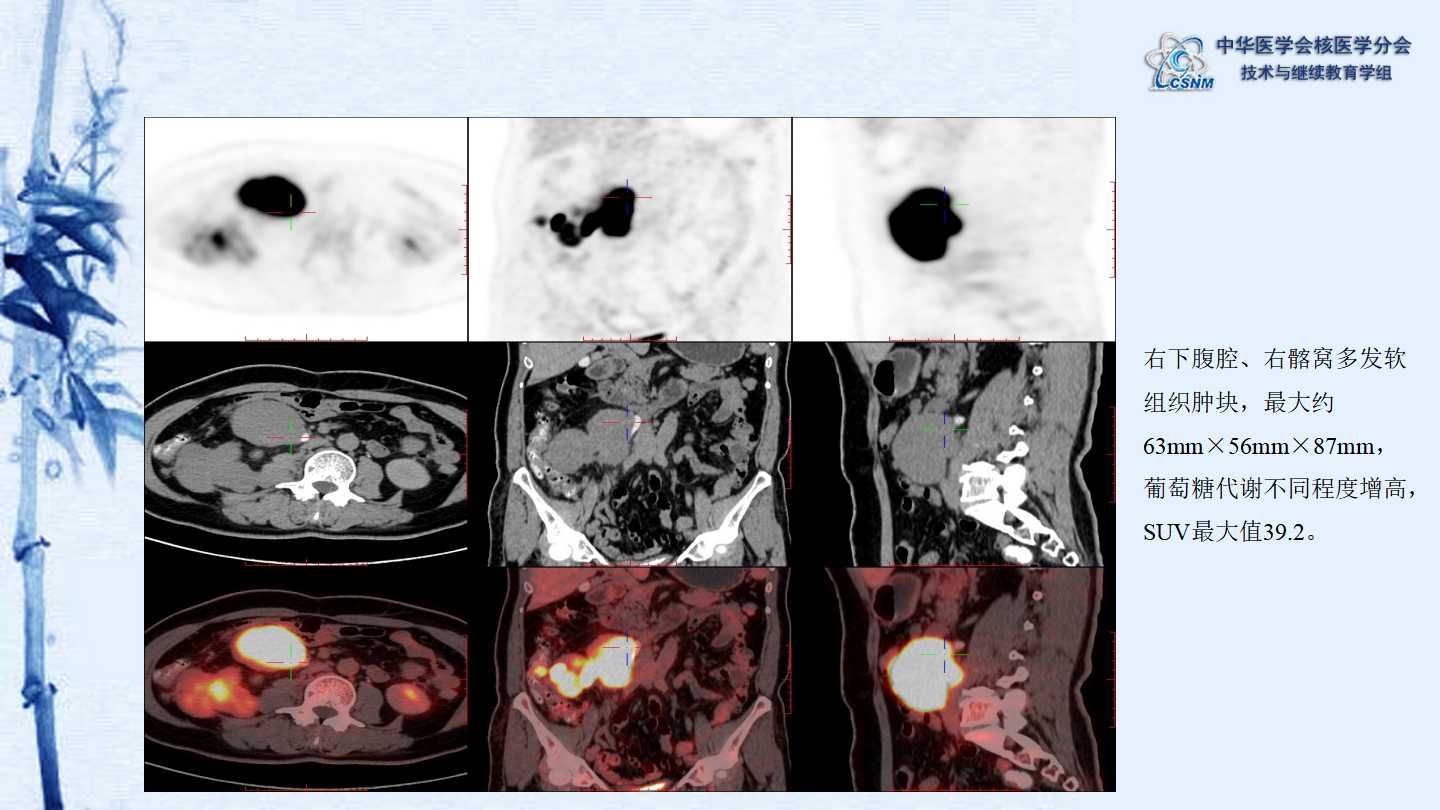

【CSNM继教学组】病例E51-邢岩-结肠炎性肌纤维母细胞瘤18F-FDG PET/CT显像